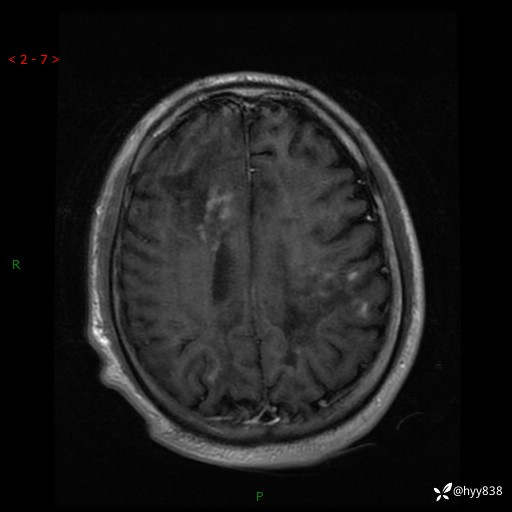

辅助检查:MRI

MRI T2WI

磁敏感成像